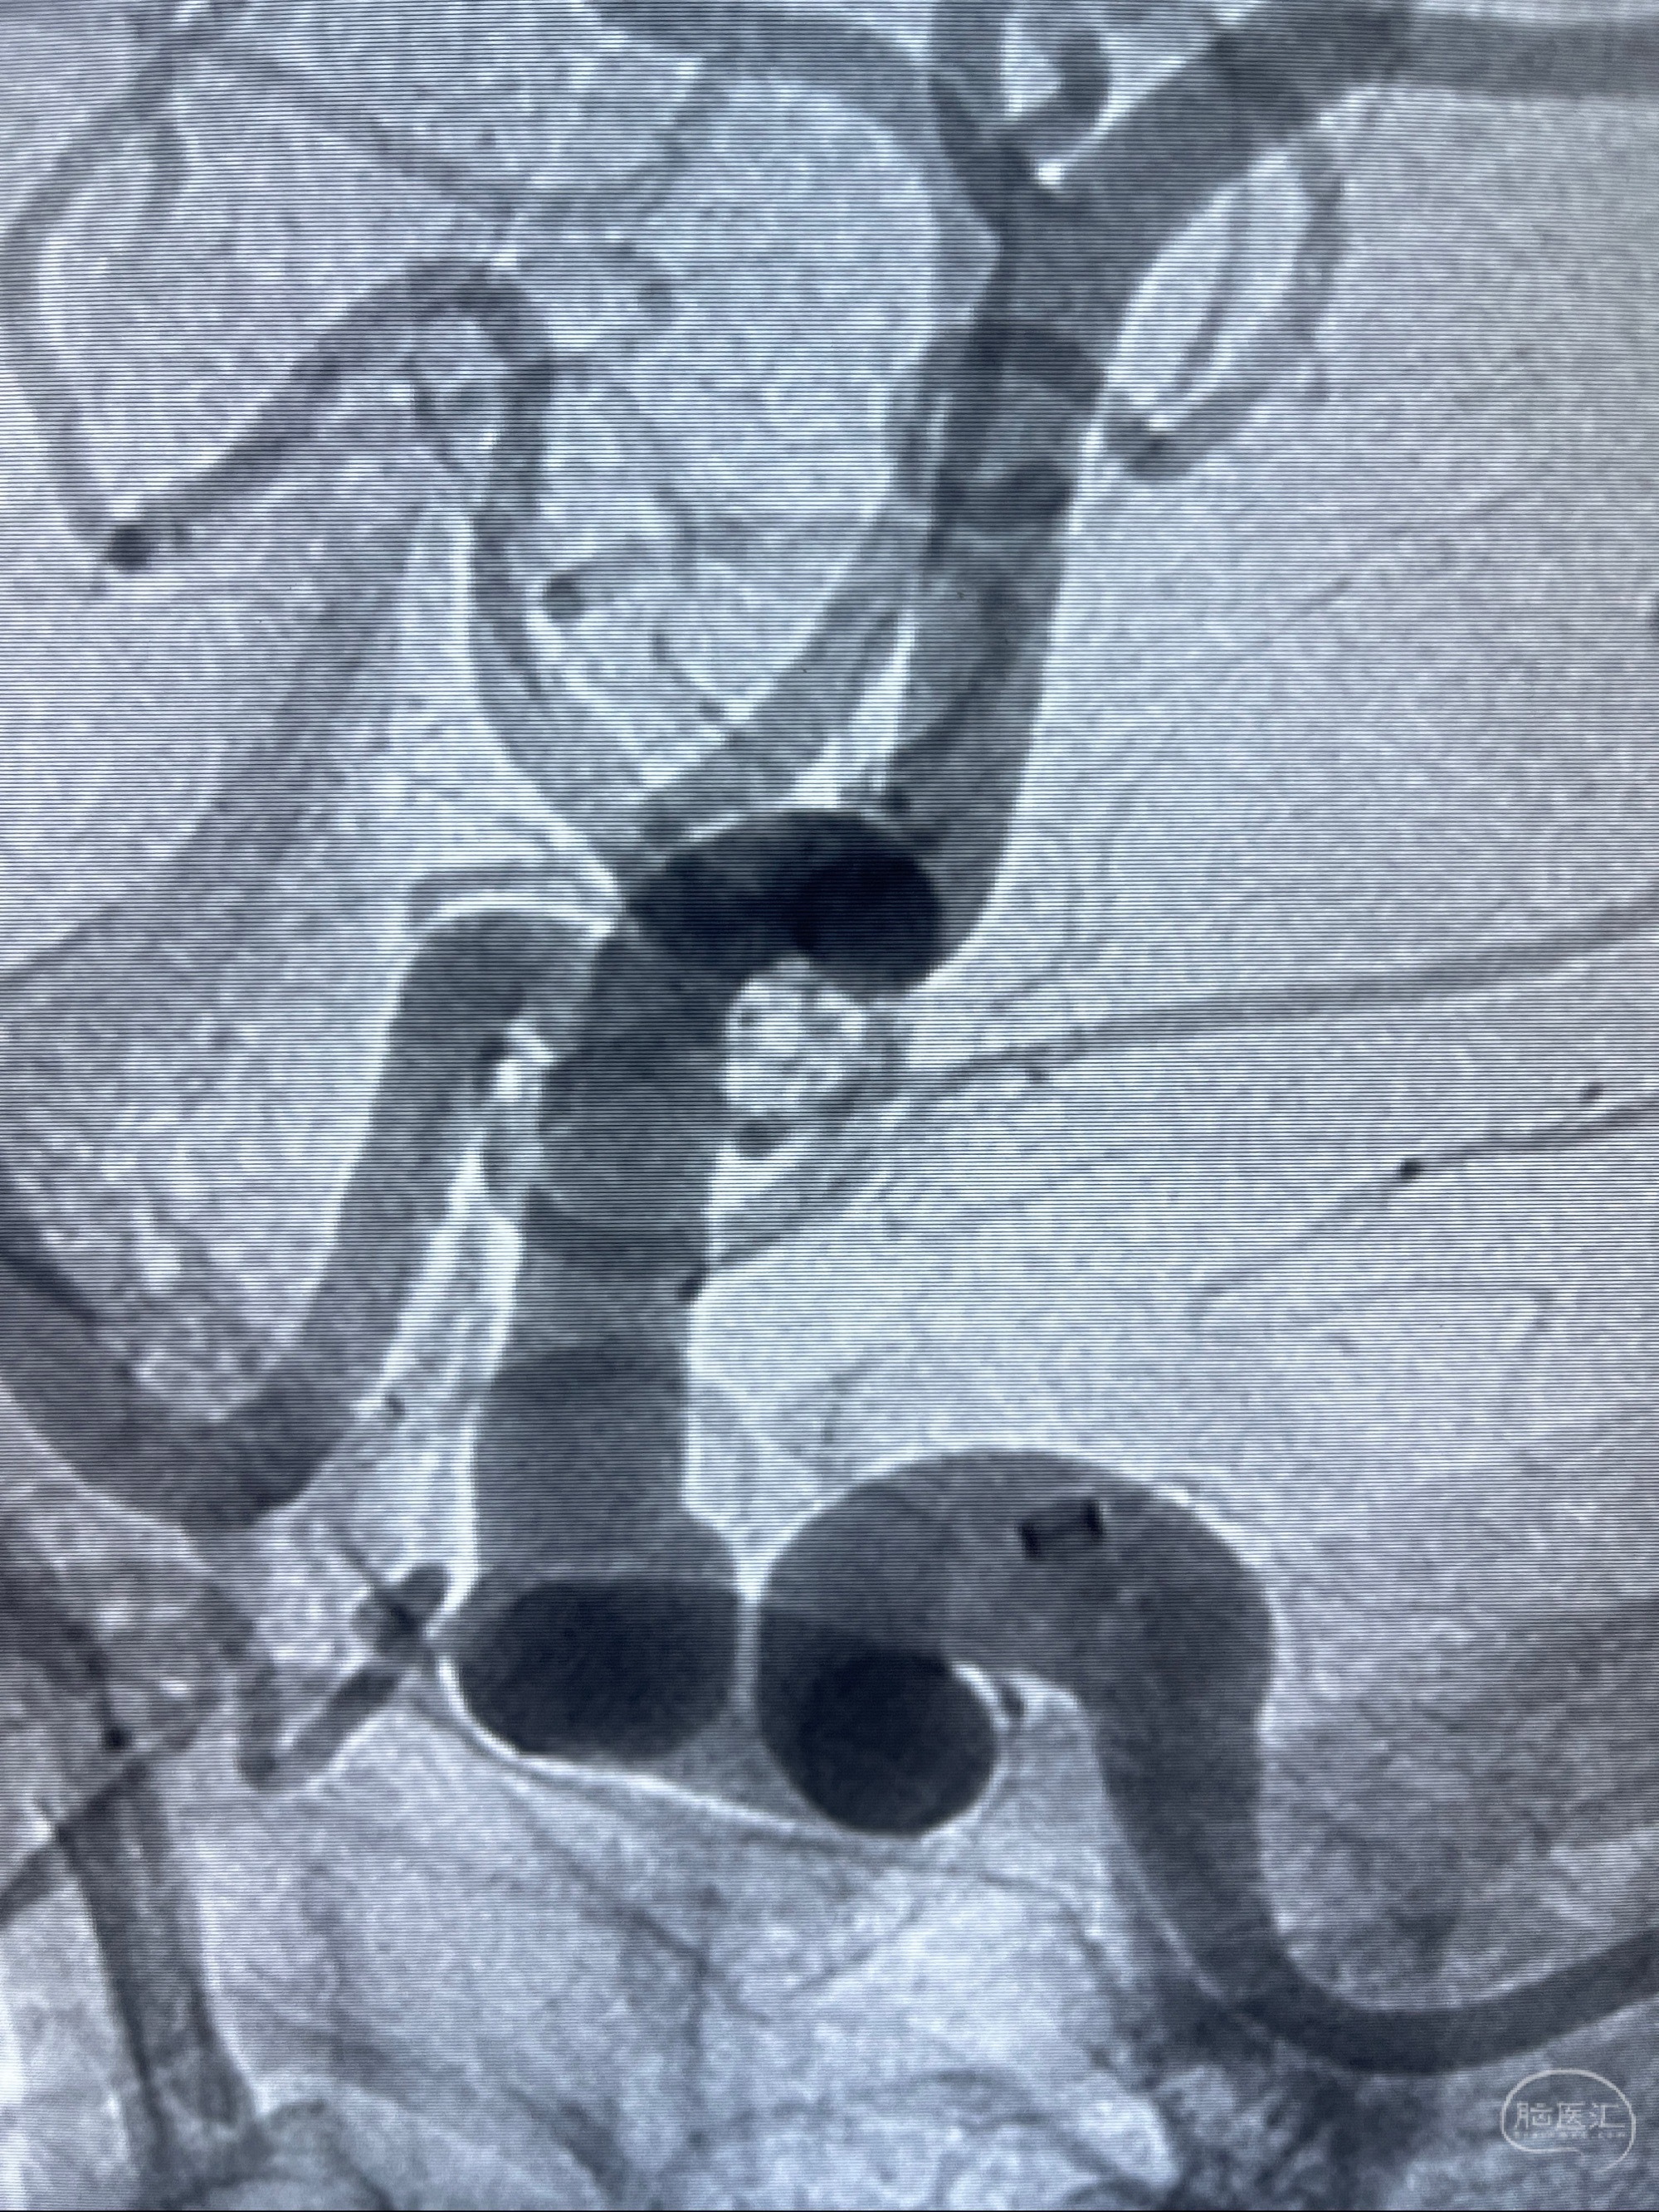

2023.07.25 泰州市人民医院查头颅CTA提示右侧C6段瘤样突起,建议DSA检查;

CTA示:右侧颈内动脉C6段见指向下方的突起,余左侧颈内动脉、双侧椎动脉、大脑前动脉、大脑中动脉、大脑后动脉及基底动脉走形正常,未见明显扩张及狭窄,局部未见明显瘤样扩张。

2023-07-27全脑血管造影:双侧颈内动脉眼动脉段动脉瘤,右侧较大